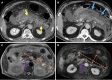

Endoscopic retrograde cholangiopancreatography (ERCP) is a cornerstone procedure for the diagnosis and management of pancreatic and hepatobiliary diseases. Although its diagnostic role has been increasingly supplanted by noninvasive imaging modalities such as magnetic resonance imaging (MRI) and magnetic resonance cholangiopancreatography, the therapeutic applications of ERCP have continued to expand. ERCP is widely used and has a generally favorable safety profile. However, it is important to recognize expected post-procedural imaging findings and serious complications that can arise. The increasing complexity of therapeutic interventions and the growing volume of procedures have led to a higher incidence of complications that often present with overlapping clinical and laboratory features, underscoring the critical role of imaging in differential diagnosis. This review focused on the typical normal ERCP findings and the imaging characteristics of common complications, including pancreatitis, bleeding, ERCP-related infections, perforations, and stent-related complications. Computed tomography (CT) is particularly valuable in timely recognition, management, and surgical decision-making for these complications. Furthermore, MRI offers a radiation-free alternative for managing complications in selected patients. Therefore, radiological modalities, particularly CT and MRI, are critical tools for the rapid diagnosis, management, and surgical decision-making processes for post-ERCP complications.